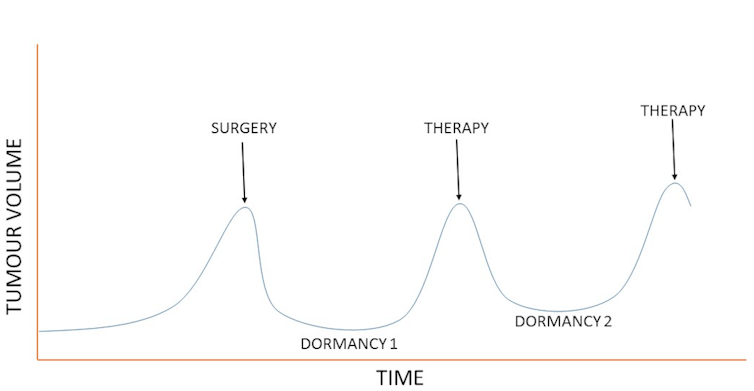

During the periods of dormancy, which could last several years, the patient will often have no symptoms and the tumour will be undetectable using the usual diagnostic tools.

It’s an unfortunate fact that, despite apparently successful treatment, cancer can sometimes come back many years after diagnosis. And this could be because some cancer cells enter into a hibernation-like state, called ‘dormancy’.

For some patients, the cancer will recur after a period of dormancy. During the periods of dormancy, which could last several years, the patient will often have no symptoms and the tumour will be undetectable using the usual diagnostic tools.

Dormancy is a stage in cancer progression where the cells cease dividing but survive in a quiescent state while waiting for appropriate environmental conditions to begin proliferation again.

During the periods of dormancy, cancer cells reshape their genetic make-up and get ready for the next stage of progression. Without dormancy, cancer cells would not be able to survive in a new environment or become resistant to the attacks of the immune system.

To understand why dormancy is useful to cancer cells, we need to examine the factors that can stop tumour progression. Cancer cells face three main challenges to their survival and growth. First, they need to deceive the immune system, which is able to eliminate most tumours. Second, they need to survive anti-cancer therapies, and, third, ...

Does cancer use the accelerator?

Cancer has always been thought of as something that grows rapidly and uncontrollably, but this view may be wrong. New evidence suggests that cancer alternatively uses the "accelerator" and the "brake" in order to survive. If you plot the growth of prostate cancer tumour progression over years, you get a graph that looks something like this: ...

Until recently, we knew very little about these periods.

Can you detect dormant cells?

Detecting dormant cells is not easy, though. Dormant tumours are often small and don't produce symptoms, so patients are often unaware of them and conventional diagnostic tools are unable to "see" them. Also, dormant cancer cells are often in slow-metabolism mode, like hibernating animals.